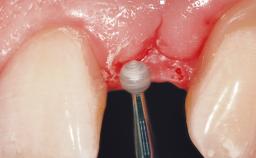

After flapless tooth extraction and a healing period of 6 weeks, a standard-diameter one-piece implant is placed. A gap between the implant and the facial bone wall is filled with autogenous bone chips harvested from the anterior nasal spine and covered with DBBM particles. Contour augmentation on the facial aspect is achieved using DBBM particles and a collagen membrane, according to the principles of guided bone regeneration (GBR). The flap is coronally repositioned for semisubmerged healing.